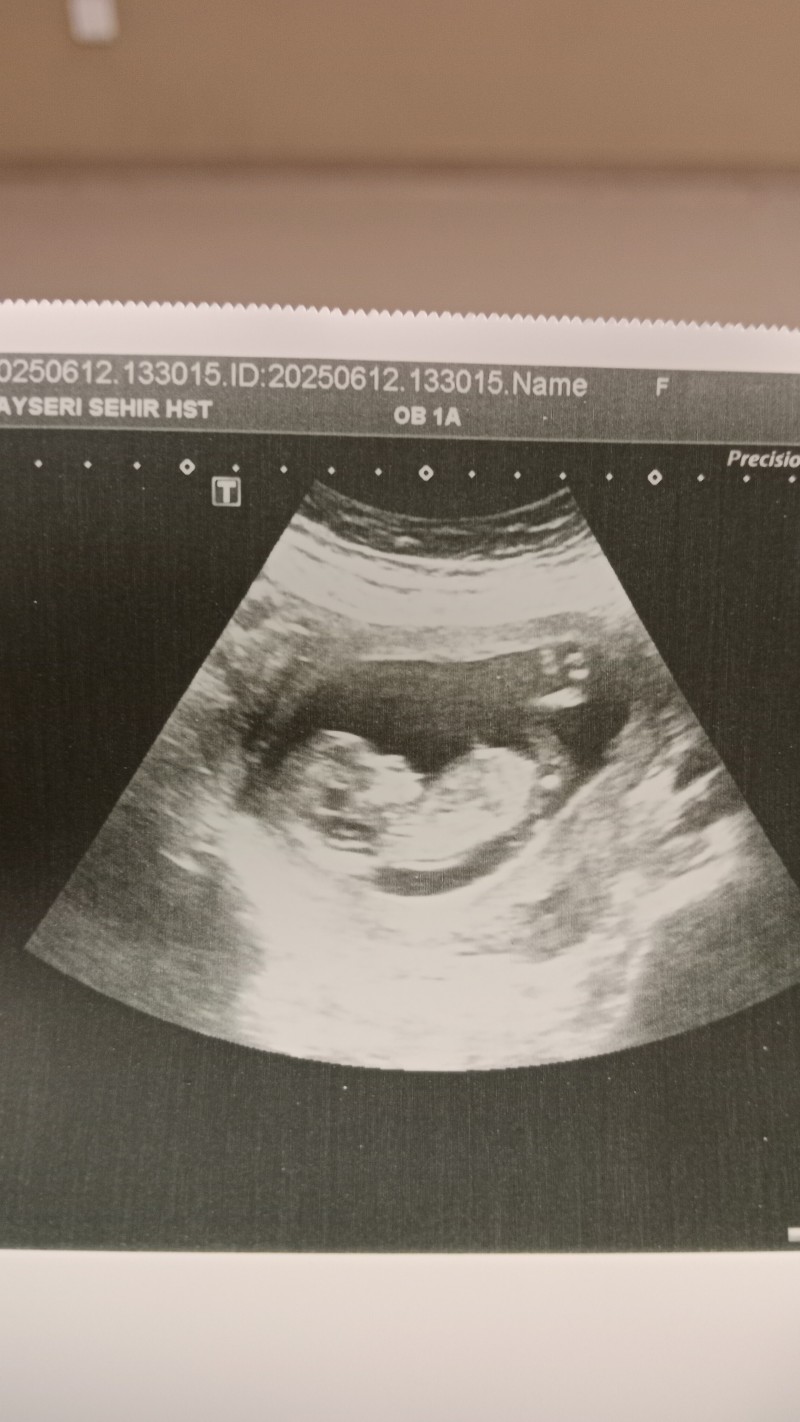

14+2 haftalık 2. gebeliğim  3 yaşında oğlum var arkadaşlar cinsiyetini merak ediyorum doktor net değil daha diyerek söylemedi anlayan varsa bakabilir misiniz rica etsemm teşekkürler 🌸🌸

Bence erkek bebiş

Bence kız benimde böyleydi biz erkek sandık kız çıktı